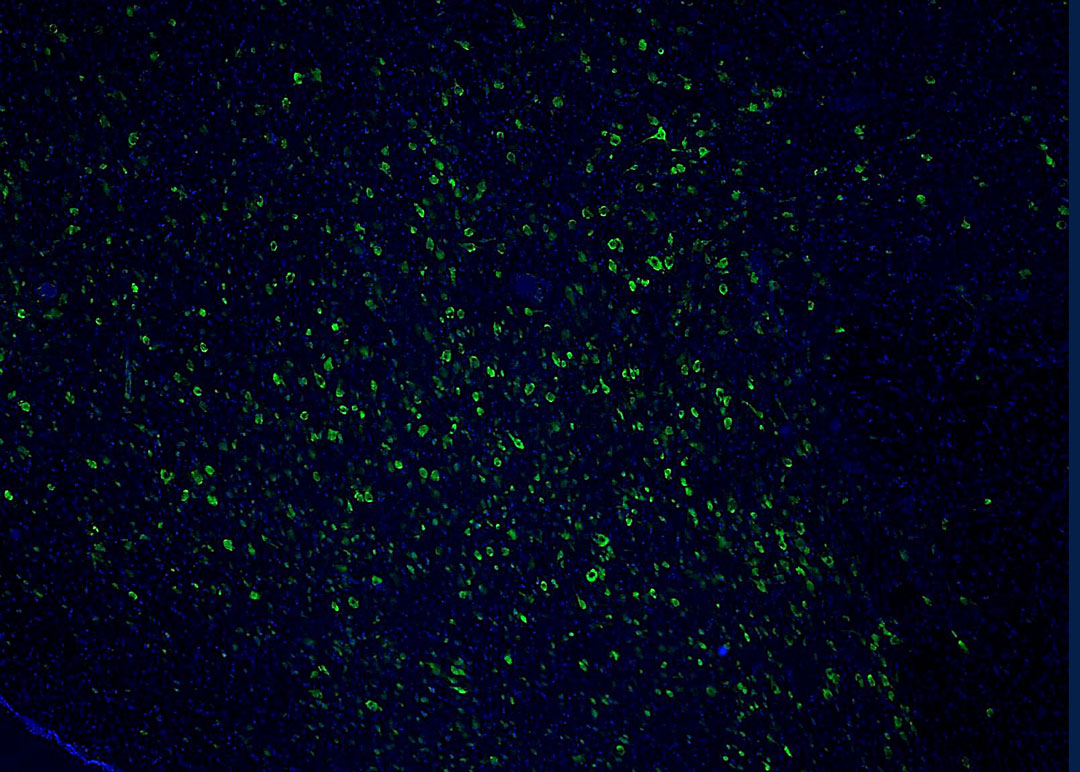

Microscopic image of human histaminergic neurons

Neurons that promote wakefulness in the brain of an Alzheimer's patient (green). There are far fewer functioning neurons that would be seen in a healthy brain, indicating that the awake system is weakened in this patient. Image by Grinberg Lab

The lethargy that many Alzheimer’s patients experience is caused not by a lack of sleep, but rather by the degeneration of a type of neuron that keeps us awake, according to a study that also confirms the tau protein is behind that neurodegeneration.

“We were able to prove what our previous research had been pointing to – that in Alzheimer’s patients who need to nap all the time, the disease has damaged the neurons that keep them awake,” said Lea Grinberg, MD, PhD, a neuropathologist who, along with psychiatrist Thomas Neylan, MD, is a senior author on the study, which appears in the April 4, 2022, issue of JAMA Neurology.

“It’s not that these patients are tired during the day because they didn’t sleep at night,” noted Grinberg. “It’s that the system in their brain that would keep them awake is gone.”

Grinberg’s team developed the hypothesis that Alzheimer’s patients were having trouble staying awake, after discovering a set of neurons that keep us awake and that are affected in Alzheimer’s from the onset of the disease.